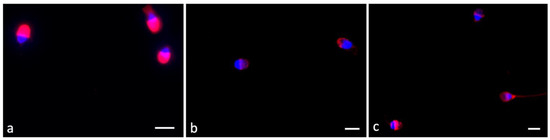

2.4. Ryanodine Receptor Localization

5.7. Immunofluorescence of Ryanodine Receptor

| Control (2 h) | F4-NeuroPs (2 h) | Control (4 h) | F4-NeuroPs (4 h) | Statistics | |

|---|---|---|---|---|---|

| sperm with diffuse fair signal% | 62 (60.50–63.50) | 10 (10–13) | 23 (22–24) | 10 (8.50–13) | C2 vs. F4-2, p = 0.001 C4 vs. F4-4, p = 0.001 C2 vs. C4, p = 0.001 F4-2 vs.F4-4, p = 0.981 |

| sperm with absence of signal% | 23 (20.25–25.75) | 10 (10–13) | 12 (10.50–13.50) | 14 (10.75–15) | C2 vs. F4-2, p = 0.001 C4 vs. F4-4, p = 0.865 C2 vs. C4, p = 0.001 F4-2 vs.F4-4, p = 0.527 |

| sperm with mitochondrial signal % | 6 (4.25–9.25) | 70 (68–73.50) | 38 (36.50–39.50) | 25 (25–25.75) | C2 vs. F4-2, p = 0.001 C4 vs. F4-4, p = 0.001 C2 vs. C4, p = 0.001 F4-2 vs.F4-4, p = 0.001 |

| sperm with dotted signal in tail | 8 (8–9.50) | 9 (6.50–11.50) | 27 (26–28) | 53.50 (50.50–56.50) | C2 vs. F4-2, p = 0.999 C4 vs. F4-4, p = 0.001 C2 vs. C4, p = 0.001 F4-2 vs.F4-4, p = 0.001 |